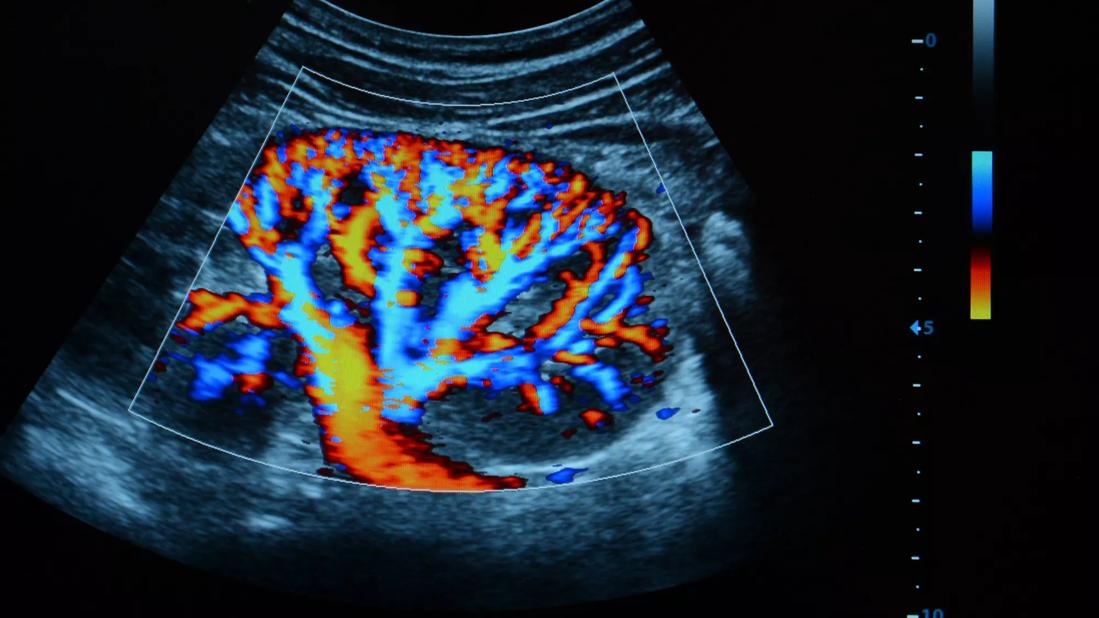

Ultrasound of kidney

The research program at the Glickman Urological & Kidney Institute (GUKI) continues to attract funding for research initiatives aimed at discovering new diagnostic and treatment options for kidney disease.